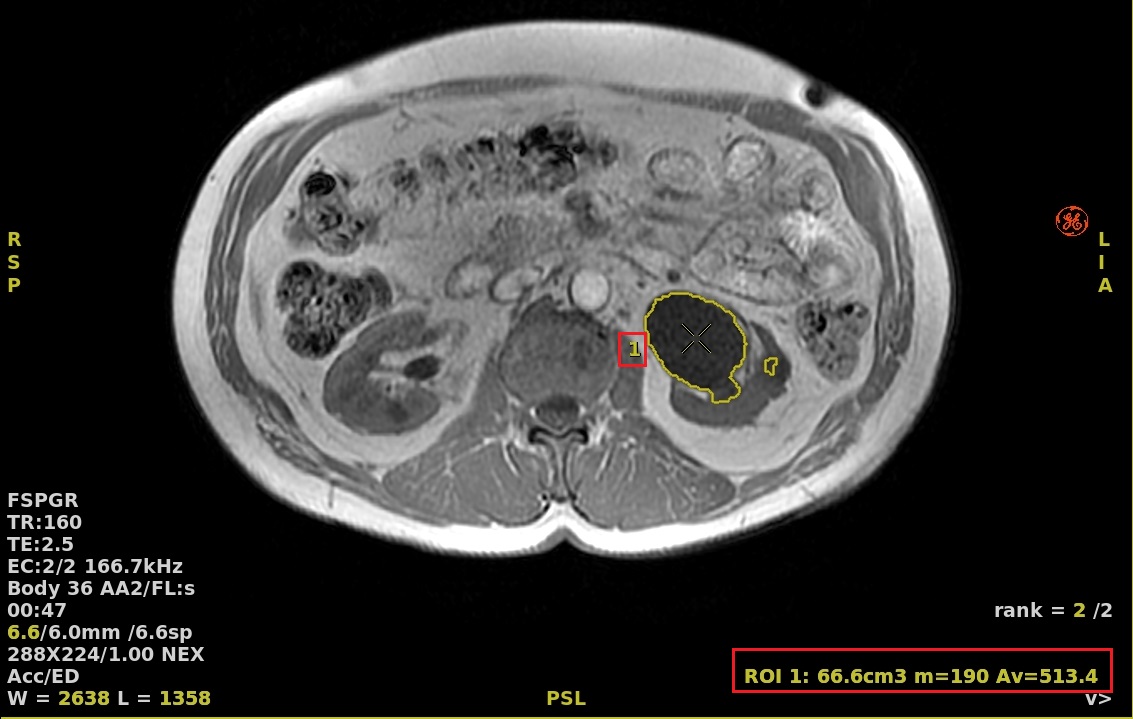

2. Do not click the Threshold option box and click in the center of the structure.

Figure 4. Auto Contour deposited in center of area of interest